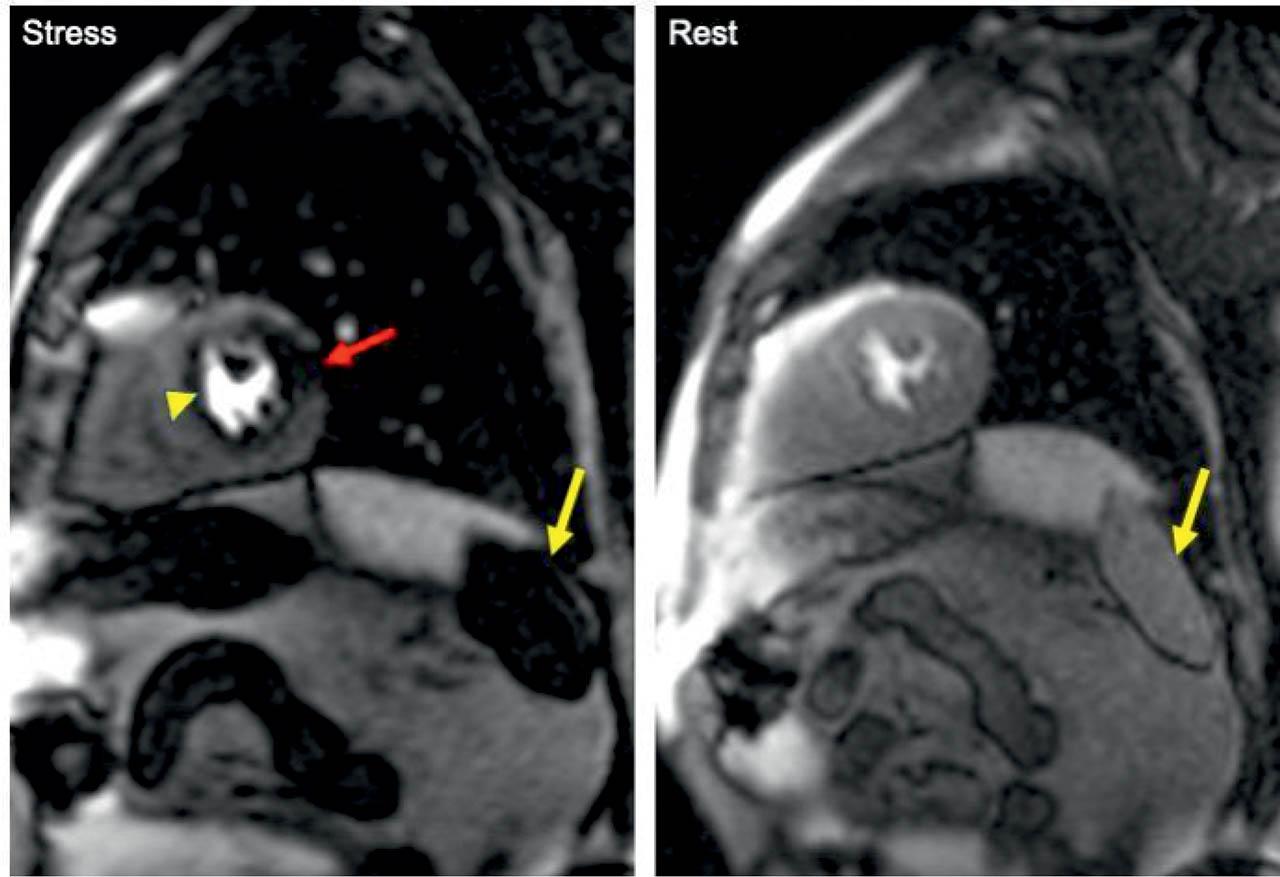

An adequate vasodilatory stress was defined when the patient experienced adenosine related symptoms (flushing, headache, chest pain/pressure palpitations, and breathlessness) and an increase in heart rate by >10 bpm. Additionally, the efficiency of the vasodilatory stress was verified with the splenic switch-off (SSO) phenomenon13 (Figure 2).

Short-axis mid-ventricular slices acquired during stress and rest, showing the splenic switch-off phenomenon, defined as a visible decrease in splenic signal intensity during adenosine stress as compared to rest (yellow arrow). During adenosine-induced hypotension, the splenic blood flow is reduced presumably due reactive sympathetic vasoconstriction. During stress, a perfusion defect is seen on the lateral wall (red arrow). This defect is no longer seen on rest perfusion acquisition. The yellow arrowhead indicates a dark-rim artifact which is the most common artifact seen in stress perfusion CMR.

When the adequacy of stress response to adenosine is questionable, the SSO phenomenon may be employed to define adequate vasodilator stress. This is defined as a visible decrease in splenic signal intensity during adenosine stress as compared to rest (Figure 2). During adenosine-induced hypotension, the splenic blood flow is reduced presumably due reactive sympathetic vasoconstriction13. In our cohort, one of the patients who did not meet the clinical criteria for adequate adenosine response, had a reliable SSO appearance, however, for safety reasons, the test was reported as equivocal.